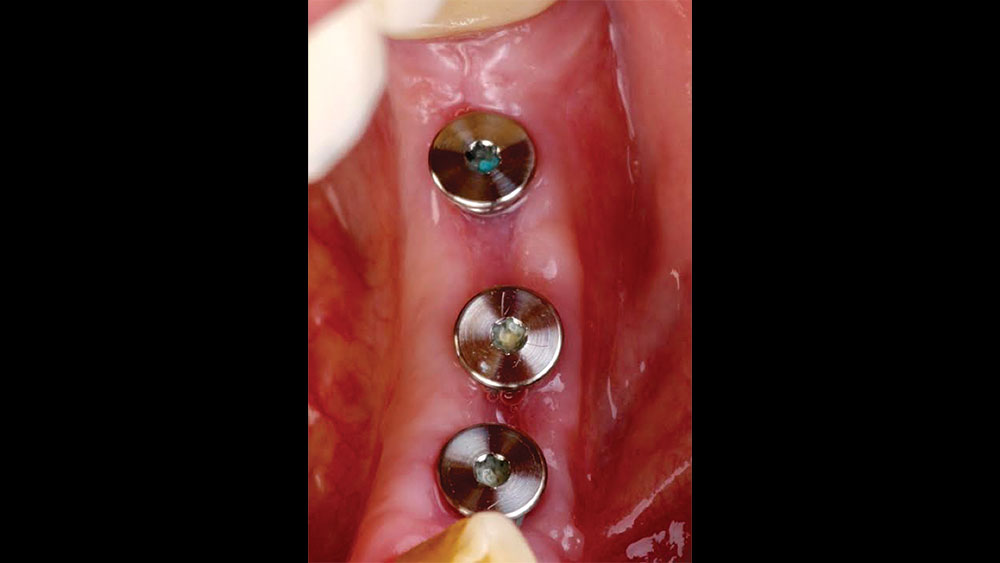

The patient selected implant treatment to replace her teeth. Screw-retained crowns were chosen instead of a cementable restoration, primarily due to the ease of retrievability afforded by screw retention. Because the posterior location of the restorations required resistance to occlusal forces as well as acceptable esthetics, I selected BruxZir® zirconia as the material; its high flexural strength and natural translucency fulfilled both requirements.

The question then became whether to use a splinted restoration in the form of a BruxZir screw-retained bridge, or unsplinted BruxZir screw-retained crowns. An assessment of this patient, as well as the pros and cons of both restoration types as previously outlined, led to the decision that an unsplinted restoration was the preferred treatment in this case. The key factors in this choice were as follows:

• The opposing dentition for this patient was a full denture. This meant that the extra stability and bite force distribution provided by a splinted restoration was not a requirement here, and I was able to remove that consideration from the equation.

• The patient had adjacent teeth on both sides of the implants, which would assist in the distribution of occlusal loads.

• As illustrated by her dental history, the patient had experienced several issues with decay in this area of her mouth. This indicated strongly that the patient most likely had challenges keeping the area clean, and any restoration that would limit her ability to clean the area could be problematic.